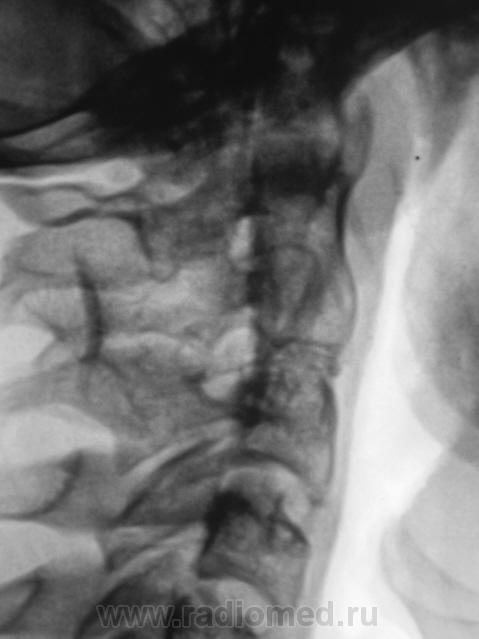

Подросток направлен в рентгеновский кабинет с диагнозом "сколиоз"...

Сколиоз-то сколиоз, но генеза "аномального".

Это синостоз тел верхних шейных позвонков и С6-С7? И боковые клиновидные полупозвонки в верхнегрудном отделе? Это синдром Клиппеля-Файля? А может и Шпренгеля...

Поражает, что только сейчас выявлена такая выраженная дисплазия..там видимо и по органам проблемм хватает..

Совершенно верно. Ведь детей и подростков "смотрят" каждый год. Возникает вопрос, как смотрят и каким "органом"?

Разумется аномалия. А ведь в карточке, наверно все аккуратно записано.

Увы, по "данному поводу" карточка девственно чиста.